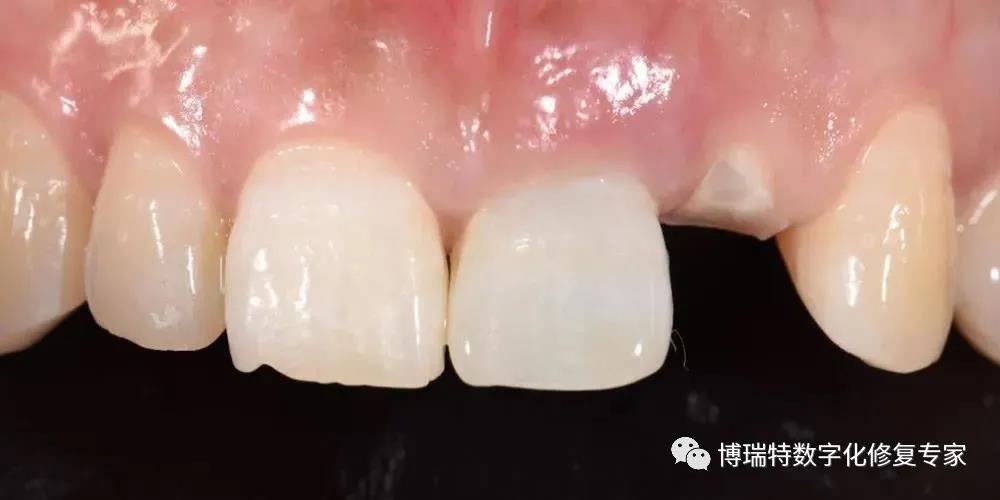

8226; 11、12一度松动,叩诊不适;

8226; 21牙冠三度松动,21牙冠冠向移位1.5mm,叩诊(+);

8226; 22冠根折,唇侧断面至龈下3mm,唇侧颈部凹陷;

8226; 高位笑线,牙龈色粉,质韧,无明显红肿;

8226; 薄龈生物型,角化龈宽度充足,龈缘高度不协调;

8226; 21龈缘根向移位约1mm;